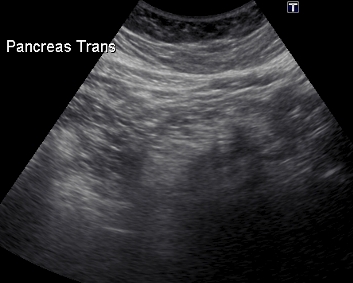

УЗИ диагностика кольцевидной поджелудочной железы: что важно знать